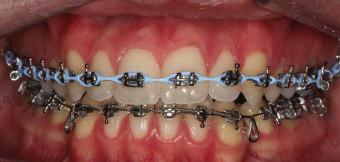

20 Dental Tribune Bulgarian Edition / октомври 2022 г. П ациентите със завършен растеж и скелетни проблеми обикновено представляват предизвикателство за ортодонт ската практика. Необходимостта от изваждане на зъби в комбинация с особеностите на възрастовата ортодонтия изисква особено внима ние. Фокусът върху критично важното значение на позицията на долните резци във връзка с дългосроч ната стабилност и постигането на оптимални оклузални взаимоотношения при затварянето на екстракционните пространства лесно може да излезе извън контрол. Когато към тези чисто кли нични проблеми се добави и стресът от натоваре ната практика, предизвикателството става още по-голямо. Всички тези фактори налагат използ ването на доказан подход с ясни и последовател ни стъпки, в което се разкрива силата на дисциплината „Алекзандър“ – предвидим протокол през целия процес на елиминиране на ротациите, ниве лиране на дъгите, затваряне на екстракционните пространства и финализиране на случая. Именно такъв е и случаят, който презентираме –екстракционен, скелетен клас 3 при възрастен па циент, лекуван по системата „Алекзандър“. ПРЕДВИДИМИ РЕЗУЛТАТИ ПРИ ПАЦИЕНТИ СЪС ЗАВЪРШЕН РАСТЕЖ И СКЕЛЕТЕН КЛАС 3, ИЗПОЛЗВАЙКИ ЕКСТРАКЦИОННО ЛЕЧЕНИЕ ПО ДИСЦИПЛИНАТА „АЛЕКЗАНДЪР“ Д-р Радой Димитров, България Преди започване на лечение клиничен случай | ортодонтия Фиг. 1а–1e Преди започване на лечение. Пациентът пристига в практиката с основното оплакване от невъзмож ност за нормално дъвчене. Снета е цялата необходима диагностична ин формация. Фиг. 1f–1h Снимки в профил и анфас. Фиг. 1i–1k Панорамна снимка, телерентгенография и анализ на телерент генография. Фиг. 1а Фиг. 1d Фиг. 1f Фиг. 1g Фиг. 1h Фиг. 1e Фиг. 1b Фиг. 1c Фиг. 1i Фиг. 1j Фиг. 1k

21Dental Tribune Bulgarian Edition / октомври 2022 г. ДИАГНОСТИЧНИ РЕЗУЛТАТИ: 1. Възраст на пациента: 21 години 2. Скелетен клас III (ANB 0) 3. Зъбен клас 3 4. Ръбцова захапка във фронта, кръстосана в дисталните участъци 5. Тясна горна челюст 6. Overjet – 0 мм, Overbite – 0 мм 7. Несъответствие на горната с долната средна линия 8. Единични контакти в ЦО 9. Хиподивергентен тип на растеж SN/MP – 33.5 10. Неравен гингивален контур 11. Неравна линия на усмивката 12. Тенденция за рецесии в долен фронт ПРЕПОРЪЧИТЕЛНО ЛЕЧЕНИЕ: Пълно ортодонтско лечение с метални брекети „Алекзандър“ Корекция на клас 3 захапката в областта на кучешките зъби с екстракция на първите пре молари в долна челюст Корекция на кръстосаната захапка в дистални участъци Коригиране на ръбцовата захапка във фронта Подобряване на ОJ и OB на пациента Стрипинг в долен фронт Подреждане на зъбите в горната и долната челюст Професионално хигиенизиране и профилактични дентални прегледи са препоръчителни на всеки 6 месеца. 1-ви месец След 1 месец са залепени брекети в горната челюст – поставена е еластична дъга. 016 NiTi. В долната челюст са елиминирани ротациите, поставена е стоманена дъга. 016SS, закалена с ток, и еластична верижка за затваряне на пространствата. 3-ти месец В долната челюст е поставена трета дъга – 17 x 25 NiTi с къси лигатури и верижка

В горната челюст се затварят пространствата с дъга .016SS и верижка. 5-и месец На 5-ия месец след залепяне на брекетите в долната челюст е поставена стоманена дъга 16 x 22 SS с четвъртито сечение, омега луп и тай бек. В горната челюст е поставена дъга 17 x 25 NiTi. Поради липсата на стабилни оклузални контакти са поставени лингвални верижки в областта на моларите, за да се предотврати нежелана ротация на 7-ите зъби. 6-и месец На 6-ия месец от началото на лечението са екстрахирани долните първи премолари, поставена е дъга 16 x 22 SS със затваряща чупка teardrop. Чупката се активира всеки месец по 1 мм с чинч-бек. клиничен случай | ортодонтия СТЪПКИ НА ЛЕЧЕНИЕТО Начало на лечението Лечението започва с поставяне на апарат за бърза експанзия в горната челюст. През първия месец от лечението са направени 24 оборота на апарата за експанзия. Залепени са брекети в долната челюст, поставена е дъга 17x25 CuNiTi, като са предпи сани клас 3 ластици (1/4”,4 1/2 oz) по време на сън, за да се осигури контрол върху торка на долните резци. Фиг. 2а Фиг. 3a Фиг. 4a Фиг. 3b Фиг. 4b Фиг. 3c Фиг. 4c Фиг. 3d Фиг. 4d Фиг. 3e Фиг. 4e Фиг. 5a Фиг. 5b Фиг. 5c Фиг. 5d Фиг. 5e Фиг. 6a Фиг. 6b Фиг. 6c Фиг. 6d Фиг. 6e Фиг. 7a Фиг. 7b Фиг. 7c Фиг. 7d Фиг. 7e Фиг. 2b Фиг. 2c Фиг. 2d

Dental Tribune Bulgarian Edition / октомври 2022 г.22 клиничен случай | ортодонтия 14-и месец В горната и долната челюст са поставени последни стоманени дъга с омега луп и тай бек – 17 x 25 SS с четвъртито сечение. Назначени е ластик за средната линия в комбинация с клас 3 ластик (1/4”, 6 1/2 oz). Контролни рентгенографии 13-и месец Екстракционните пространства са затворени. Направена е контролна панорамна снимка за оценка позицията на корените. Взето е решение за презалепване на брекетите на 12, 22 и пръстените на 36 и 46. 21-ви месец Средната линия в горната и долната челюст съвпадат. Ластиците са спрени. Свалени са пръстените и брекетите в горната и долната челюст, зигзаг ластици не са използвани поради благоприятните оклузални взаимоотношения. Фиг. 11j Ортопантомография в края на лечението. Фиг. 11k Телерентгенография след края на лечението. Фиг. 11l Анализ на телерентгенографията след лечението. Фиг. 11m Последователност на дъгите в горната и долната челюст Фиг. 11n Суперимпозиция на PreOp и PostOp ортопантомографии. 10-и месец Затварянето на пространствата е предвидимо и контролирано, без да се отварят пространства в зъбната дъга. Фиг. 8a Фиг. 8b Фиг. 8c Фиг. 8d Фиг. 8e Фиг. 10a Фиг. 10b Фиг. 10c Фиг. 10d Фиг. 10e Фиг. 9a Фиг. 9b Фиг. 9c Фиг. 9d Фиг. 9e Фиг. 9f Фиг. 11a Фиг. 11f Фиг. 11j Фиг. 11l Фиг. 11m Фиг. 11n Фиг. 11k Фиг. 11g Фиг. 11h Фиг. 11i Фиг. 11b Фиг. 11c Фиг. 11d Фиг. 11e

Dental Tribune Bulgarian Edition / октомври 2022 г. 23клиничен случай | ортодонтия реклама Лечението е продължило 21 месеца. Проведено е домашно избелване с индивидуални шини. За автора: Д-р Радой Димитров завършва с отличие Факултета по дентална медицина към МУ–София през 2015 г. В продължение на 5 години работи в няколко водещи практики в София, като през 2019 г. заедно със своята съпру га д-р Траяна Димитрова основават собствена практика в гр. Гоце Делчев –Dimitrovi Dental Care. Посещава редица курсове за повишаване на квалификаци ята, но най-сериозен тласък в развитието на ортодонтската си практика получава след завършването на комплексната ортодонтска програма, воде на от д-р Иван Горялов, базирана на дисциплината „Алекзандър“ – система с повече от 50 години опит в целия свят. Д-р Димитров е член на Българския изследователски клуб „Алекзандър“. Взе ма участие като гост-лектор в симпозиума с международно участие The Power of the Alexander Discipline, който се проведе на 14–15.05.2022 г. С д-р Ди митров можете да свържете на тел. +359885 252 025. Заключение Представеният случай е ярък пример за възможностите и красо тата на дисциплината „Алекзандър“ – приложен е утвърден под ход с ясни правила и са постигнати очакваните цели. Резулта тът ще бъде дългосрочно стабилен, тъй като са спазени всички правила, които се отнасят към максимално комфортната пози ция на зъбите в края на лечението. Постигнати са красива усмив ка и стабилна оклузия. ПОСТИГНАТИ РЕЗУЛТАТИ ОТ ЛЕЧЕНИЕТО 1. Коригирана ръбцова захапка 2. Коригирана клас 3 захапка в областта на ку чешките зъби 3. Коригирана кръстосана захапка в дисталните участъци 4. Коригиран овърджет и овърбайт 5. Разширена е горната зъбна дъга 6. Подредени зъби в горната и долната челюст 7. Постигната е стабилна захапка с множество контакти в ЦО 8. Драматично е подобрена дъвкателната функ ция 9. Подобрена е линията на усмивката ДРУГИ ПРОВЕДЕНИ ДЕНТАЛНИ ПРОЦЕДУРИ 1. Домашно избелване на зъбите 2. Екстракция на мъдреците Фиг. 12a Фиг. 12b Фиг. 12c Фиг. 12eФиг. 12d Фиг. 12f Фиг. 12g Информация за дати, цени и отстъпки www.bracescourses.com 0889 22 55 01 Практически курсове лектор д-р Иван Горялов Дисциплината „Алекзандър“ ПЪТЯТ КЪМ СУПЕРУСМИВКИТЕ 100% връщане на цялата сума, ако не сте удовлетворени след преминаване на Ниво 1 Директно и индиректно залепяне на брекети Анализ, диагноза и план на лечение Лечение на клас 2 дълбока захапка Екстракционно лечение Лечение на клас 3 отворена захапка НИВО 5НИВО 1 НИВО 2 НИВО 3 НИВО 4